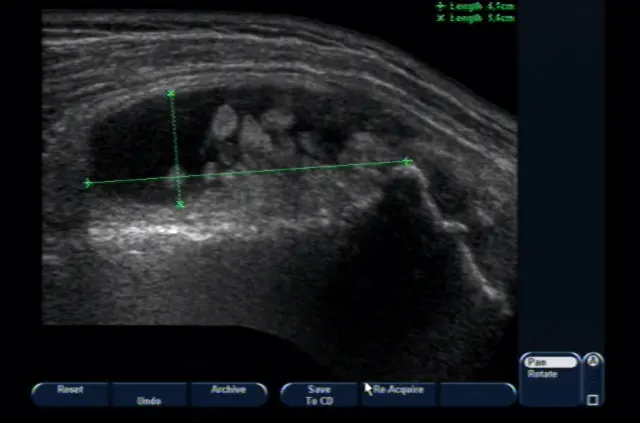

В першу чергу лікар проводить клінічний огляд, під час якого опитує пацієнта і збирає максимально детальний анамнез. Після цього лікар призначає рентгенографію хворого суглоба для виключення артрозів і інших патологій, включаючи складні пухлини. Проведення ультразвукової діагностики показує характер запальних змін, якщо такі є і загальну кількість запаленої синовіальної рідини. Завершальним етапом, перед тим, як доктор поставить діагноз, є певні лабораторні дослідження.